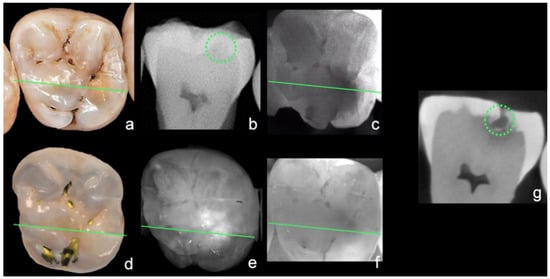

Figure 8 shows an example of all caries diagnostic methods used in this study.

Figure 8.

Example of all investigated caries diagnostic methods: visual examination (a), bitewing radiography (b), Diagnocam (c), Trios 4 (d), iTero Element 5D (e), Planmeca Emerald S (f), and µ-CT reference (g); green line shows plane of µ-CT, green circle marks caries lesion in sectional image.